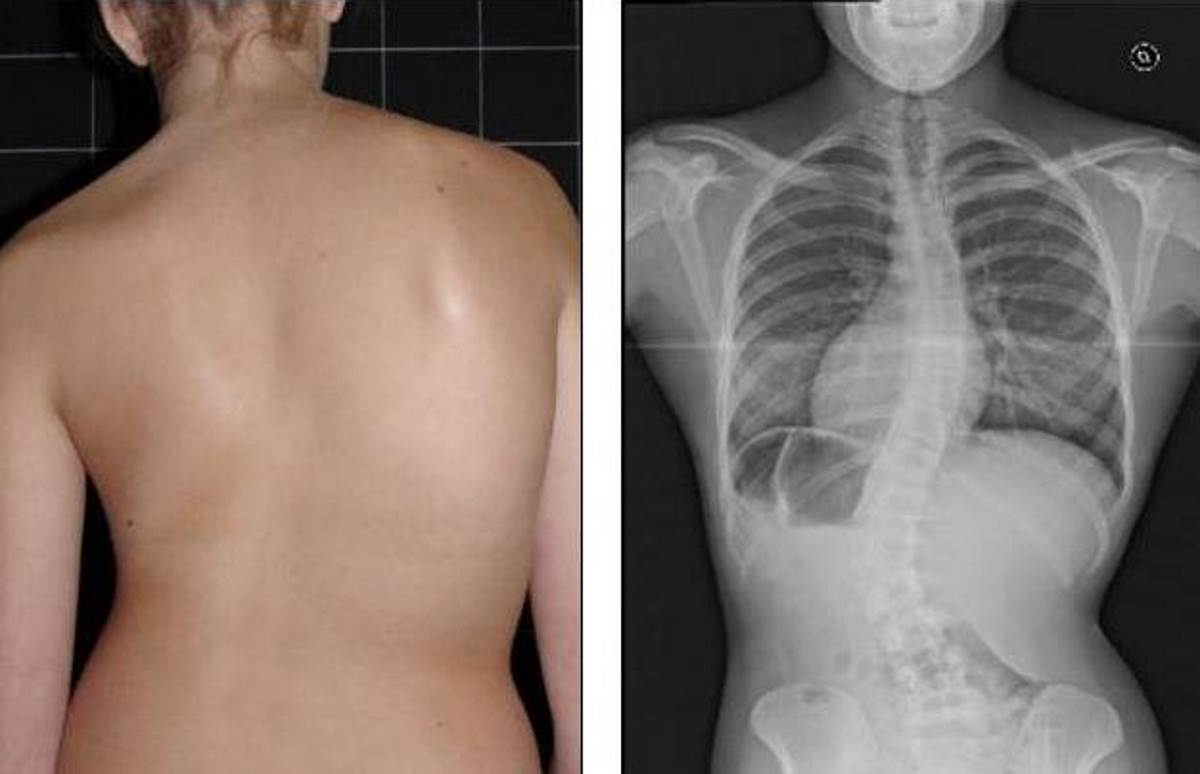

Главная Сколиоз Как выглядит сколиоз Cколиоз грудного отдела позвоночника 2 степени

Cколиоз грудного отдела позвоночника 2 степени

Полный размер 1200 × 774 пикселей Как выглядит сколиоз